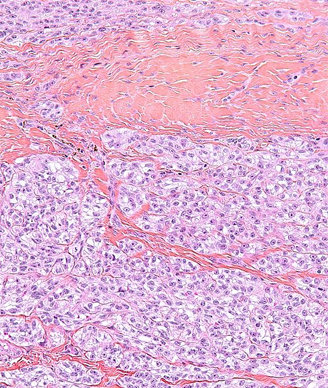

High magnification micrograph of a clear cell sarcoma in a tendon. Copyright 2012 Neprhon.